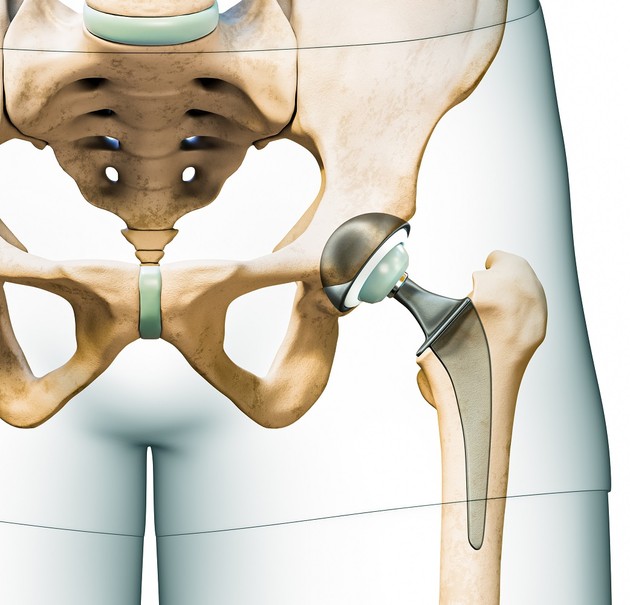

인공 고관절 전치환술은 고관절의 퇴행성 관절염이나 대퇴골두 괴사 등에 대한 치료방법으로 비구와 대퇴골두를 모두 인공 삽입물로 교체해 통증을 줄이고 기능을 회복시키는 수술이다. 수술 후 대부분의 환자는 일상으로 복귀하지만 일부는 시간이 지남에 따라 재치환술(재수술)이 필요한데, 이는 전치환술 보다 더 고난도고 예후가 좋지 않다.

비구(컵 부분)와 대퇴골두를 모두 인공 삽입물로 교체한 것을 볼 수 있다.